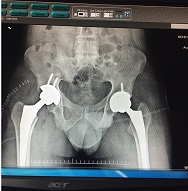

Bilateral Thr

Bilateral Thr Male